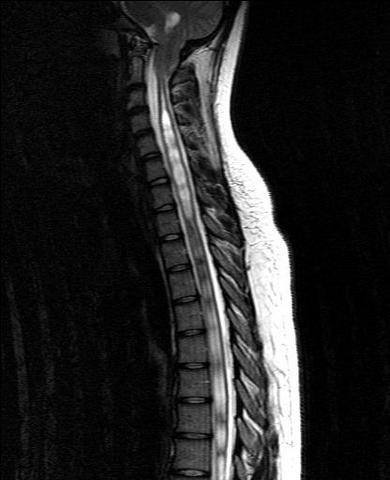

Сирингомиелия что

Сирингомиелия что 111 фотографий